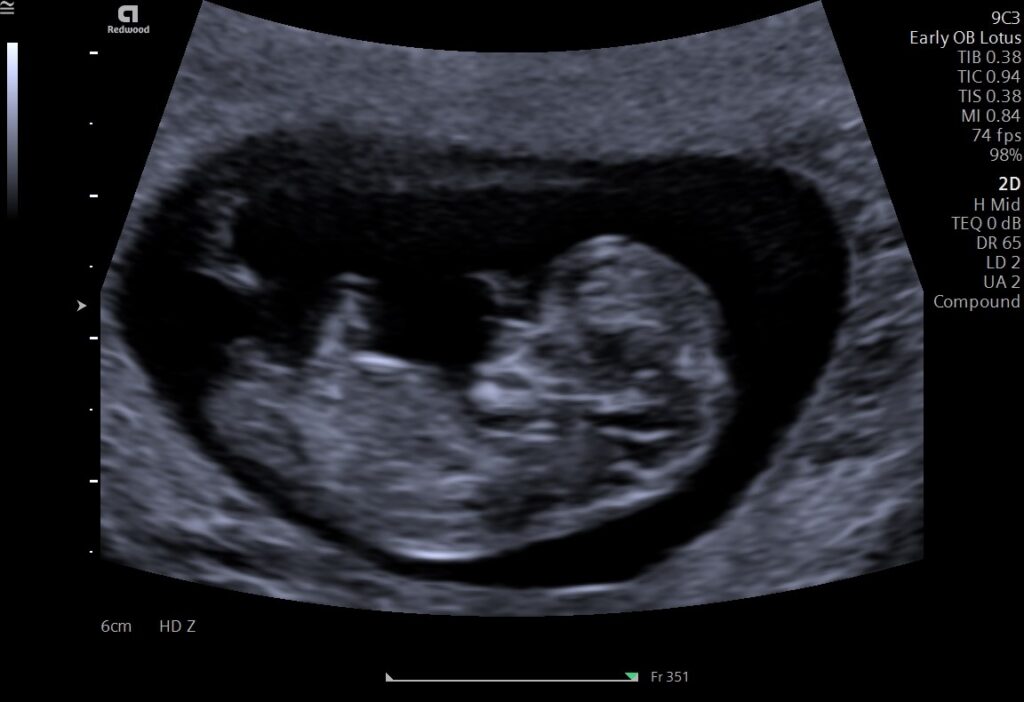

Eerste echo

Wanneer de eerste echo wordt gemaakt, rond de 7 weken, willen we een kindje zien met een kloppend hartje (mits het kindje te jong is waarbij het hartje nog moet gaan kloppen). We meten het kindje een aantal keer op om een tijdelijke uitgerekende datum te kunnen bepalen en we kijken of het kindje zich in de baarmoeder bevindt. Ook kijken we of we wellicht meer dan één kindje zien. Omdat de baarmoeder zich rond de 7 weken nog onder het schaambot bevindt wordt deze echo vaak vaginaal gemaakt. Mocht je dit liever niet willen, geef het ons even aan. Soms kan de echo via de buikwand gemaakt worden. Houdt er wel rekening mee dat wanneer we via de buikwand onvoldoende zien we de echo herhalen op een later tijdstip (wanneer je zwangerschap verder gevorderd is).